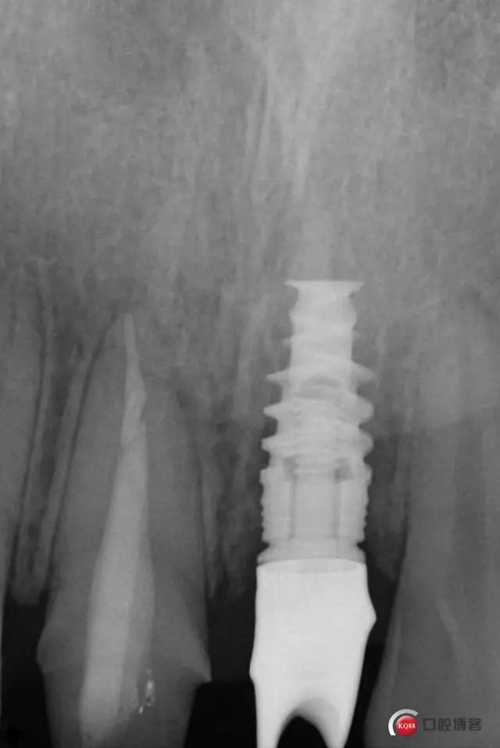

藻酸鹽對頜取模,超硬石膏灌注。發(fā)加工廠,與技工溝通注意事項(xiàng),等修復(fù)體做好后,檢查模型。是否就位,是否密合,預(yù)約患者復(fù)診戴牙,消毒修復(fù)區(qū),旋出愈合基臺,定位器指導(dǎo)安放修復(fù)基臺,試戴冠,調(diào)磨鄰接及 咬合至合適,拋光,患者滿意,加力扳手加力至30N,拍X片見就位良好,特芙蓉及暫封膏封中央螺絲孔,聚羧酸鋅粘固劑粘固,或是樹脂水門汀粘固,清理多余粘結(jié)劑,光固化樹脂封螺絲孔,拋光。術(shù)后注意隨訪。